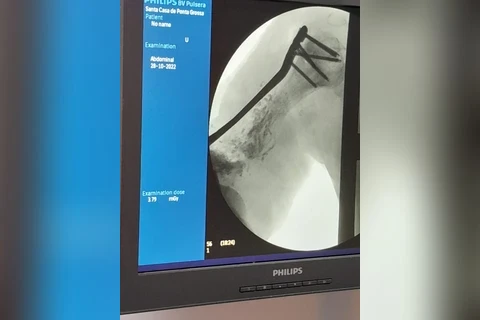

No último dia 28, a equipe de Ortopedia e Traumatologia da Santa Casa de Ponta Grossa realizou um procedimento cirúrgico inédito na região dos Campos Gerais, que consiste na correção de ossos em situações de fraturas. Neste caso, a paciente em questão fraturou o úmero (osso superior do braço), passou por diversas cirurgias em outras instituições, porém sem obter sucesso. O cirurgião Dr Carlos Miers explica a dificuldade para a realização do procedimento: “a cada cirurgia realizada a quantidade de osso disponível no braço era menor, e quando a paciente chegou até mim ela já tinha o úmero direito muito menor que o esquerdo, e com um defeito ósseo grande." A primeira etapa do tratamento consistiu em tratar a infecção, após isso foi necessário fazer um transporte ósseo com fixador externo, utilizado pela paciente durante 2 anos. Em seguida foi necessário estabilizar e fixar o úmero da parte superior até a inferior, porém não havia placa/haste disponível no mercado que supria a necessidade desta paciente “aí que começa a singularidade deste procedimento, nós em parceria com a empresa Neoortho, desenhamos e desenvolvemos uma placa personalizada especifica para a anatomia desta paciente”, explica o profissional. O projeto de personalização da placa foi realizado utilizando tecnologia de ponta através e modelos computacionais extraídos de tomografia, simulações mecânicas em elementos finitos para garantir que o material não iria falhar durante o tratamento: “após diversos testes chegou-se a versão final da placa que foi instalada na paciente durante a cirurgia”, complementa o Dr Carlos. Participaram da cirurgia os profissionais Dr Carlos Miers e o Dr Rodrigo Favaro, o procedimento foi realizado no centro cirúrgico da Santa Casa, durou 4 horas e foi um sucesso. A Instituição que é referência para 28 municípios vem traçando estratégias para cumprir sua missão de acolher e tratar o paciente respeitando sua individualidade, proporcionando uma experiência em saúde com ética, segurança, tecnologia e resolutividade. [gallery size="medium" ids="137648,137649,137650"]